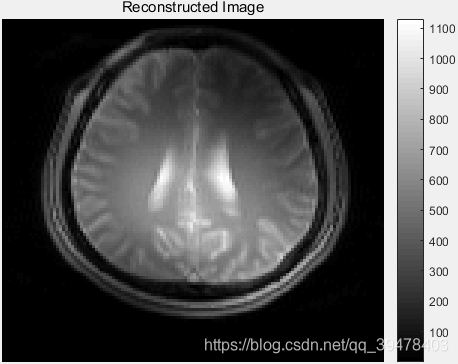

显示 RSOS 重建 MR 图像:

%recon = ifft2(ifftshift(ifftshift(grappaKspace, 2), 1)); 源代码

recon = ifftshift(ifft2(fftshift(grappaKspace))); % 120×128×5 complex double 修正

reconImage = rsos(recon); % 120×128 double RSOS 组合重建结果

显示恢复的各线圈及 RSOS 重建的相位角图像: